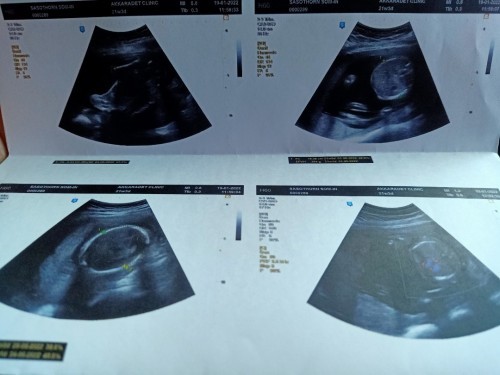

มาถึงครึ่งทาง 21week 3day น้องหนัก 394g.แล้วค่ะ แต่น้ำหนักแม่ขึ้นมา6กิโลเลย หมอนัดรอบหน้าต้องคุมน้ำหนักแล้วกลัวเบาหวานมาก น้ำหนักตั้งต้นที่60กิโล เป็นคนมีหน้าท้องหนา รู้สึกลูกดิ้นน้อยมากเลย ค่ะ อายุก็38แล้ว กำหนดคลอด29พ.ค.65 ได้ลูกชาย #ท้องแรกคะ